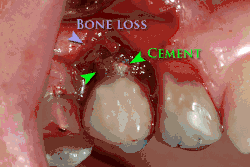

Od těchto teoretických rizik odvozujte komplikace v reálném světě. Dlouhodobá selhání jsou způsobena buď ztrátou kosti kolem zubu a/nebo dásně v důsledku periimplantitidy, nebo mechanickým selháním implantátu. Protože na implantátu není zubní sklovina, nedochází k jeho selhání v důsledku zubních kazů jako u přirozených zubů. Přestože rozsáhlých dlouhodobých studií není mnoho, několik systematických přehledů odhaduje dlouhodobou (pětiletou až desetiletou) životnost zubních implantátů na 93–98 % v závislosti na jejich klinickém použití.[1][2][3] Během počátečního vývoje zubních implantátů byly všechny korunky připevněny k zubům pomocí šroubů, ale novější pokroky umožnily umístění korunek na opěrky pomocí dentálního cementu (podobně jako při nasazování korunky na zub). Tím vznikla možnost, že cement, který unikne zpod korunky při cementaci, se zachytí v dásni a vytvoří periimplantitidu (viz obrázek níže). Ačkoli se tato komplikace může vyskytnout, nezdá se, že by u cementovaných korunek docházelo k dalším periimplantitidám ve srovnání se šroubovanými korunkami celkově.[59] U složených implantátů (dvoustupňových implantátů) jsou mezi vlastním implantátem a nadstavbou (abutmentem) mezery a dutiny, do kterých mohou pronikat bakterie z dutiny ústní. Později se tyto bakterie vrátí do přilehlých tkání a mohou způsobit periimplantitidu.